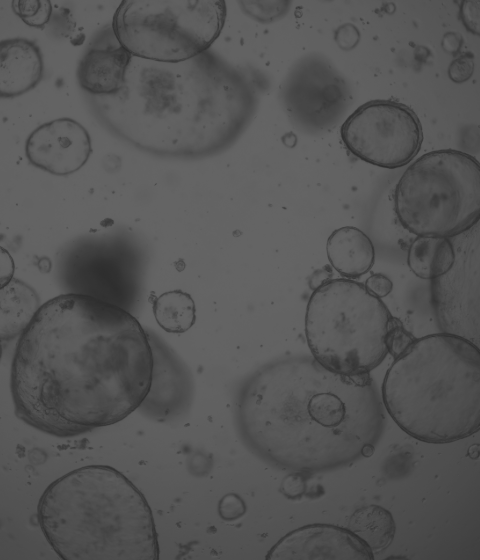

廈門模基生物科技有限公司致力于3D細(xì)胞培養(yǎng)核心原材料的研發(fā)與產(chǎn)業(yè)化升級(jí),是國(guó)內(nèi)一家從科研做起,從實(shí)驗(yàn)研究中一路走來(lái)的全流程自主研發(fā)、自主生產(chǎn)的企業(yè)。目前公司的產(chǎn)品有基質(zhì)膠、類器官培養(yǎng)基、細(xì)胞因子、3D細(xì)胞培養(yǎng)耗材、3D細(xì)胞培養(yǎng)智能顯微鏡等。公司擁有4大技術(shù)研發(fā)中心:分子克隆和細(xì)胞編輯中心、實(shí)驗(yàn)動(dòng)物中心、蛋白表達(dá)和純化平臺(tái)、類器官質(zhì)檢系統(tǒng)和自動(dòng)化。